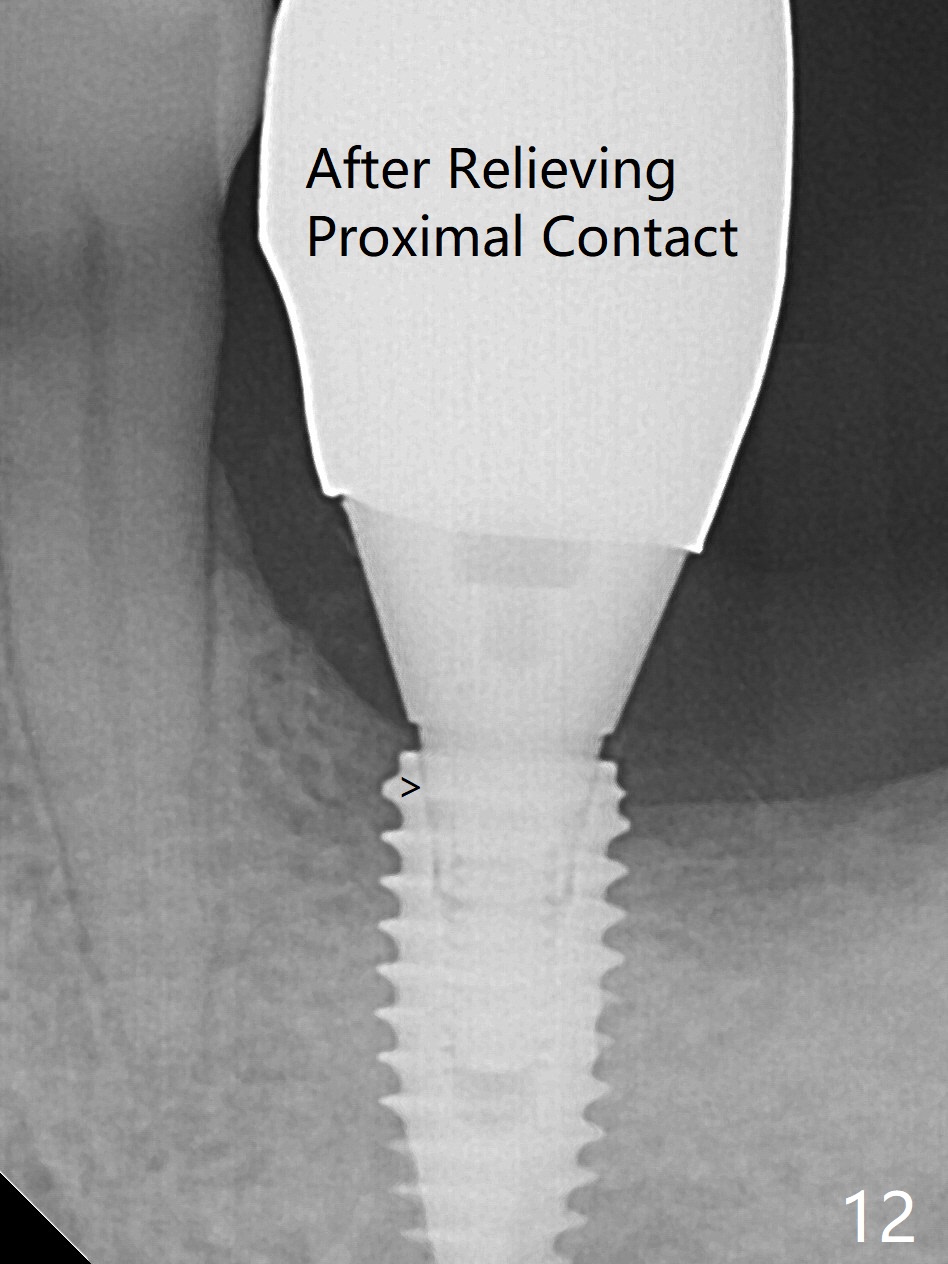

When the patient returns for #19 extraction (Fig.1), there is no 5x10 mm implant available. In fact the smaller one (4.5x10 mm) is able to achieve insertion torque >60 Ncm with more room for autogenous bone/allograft horizontally (Fig.2 *). After insertion of a definitive abutment (6.5x5.5(4) mm), more allograft is placed coronally (Fig.3 *). The gingiva that was between the mesial and distal roots before extraction (Fig.1 *) is transferred distal (Fig.4.5 *). An immediate provisional (Fig.6 P) is fabricated to close the socket opening, followed by periodontal dressing (data not shown). The latter is partially detached 2 weeks postop (Fig.7 D). When it is removed, some of possibly collagen plug is exposed distobuccally (Fig.8). When the plug is removed, some of the bone graft (Fig.9 *) is exposed distal to the provisional (P). New periodontal dressing is applied to keep the exposed graft in place. There is no apparent thread exposure 4 months postop (Fig.10). The abutment is loose 4 months post cementation, probably related to unfavorable crown/implant ratio; but when the abutment is retightened, there is a gap between it and the implant (Fig. 11 >). After relieving the proximal contact of the crown, the abutment is retightened one more time with the same gap (Fig.12 >). In fact the latter is present previously. A narrower abutment with longer cuff appears to be completely seated, probably avoiding contact with the regenerated crestal bone (Fig.13 *). If the new crown gets loose, bury a driver inside the abutment.